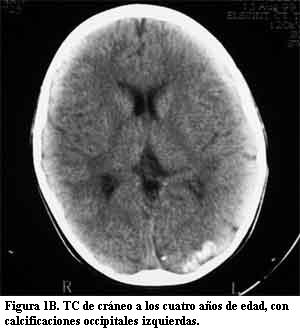

Niña de 10 años, sin antecedentes pre ni perinatales que a los 10 meses de edad, luego de un traumatismo de cráneo de intensidad leve, presentó crisis caracterizadas por vómitos, desviación óculo-cefálica a izquierda e hipotonía global, con sopor posterior, que se reiteraron en el curso de 24 horas. Su examen físico fue normal. En esa oportunidad se le realizó fondo de ojo, tomografía de cráneo (TC) (figura 1A) y electroencefalograma (EEG), que fueron normales. Evolucionó favorablemente hasta la edad de 4 años, cuando presentó nuevamente crisis epilépticas parciales complejas, con un episodio de status epilepticus. El EEG mostró signos de sufrimiento cerebral focal a nivel parieto-occipital izquierdo. En la TC se observó una imagen hiperdensa occipital izquierda (figura 1B). La resonancia magnética (RM) mostró un área de realce leptomeníngeo con el gadolinium en la misma topografía en relación con una corteza cerebral de aspecto atrófico, así como el plexo coroideo ipsilateral aumentado de tamaño (figura 2). En la angiorresonancia se observó una disminución de la señal de flujo en el seno venoso lateral izquierdo que se interpretó secundaria a trombosis (figura 3A). En la angiografía digital se comprobó que el seno venoso estaba permeable con un marcado enlentecimiento de la circulación compatible con estasis venosa y una alteración de la barrera hematoencefálica a nivel occipital izquierdo (figura 3B). Los anticuerpos antigliadina y antiendomisio fueron negativos. El estudio de los factores de la coagulación descartó una alteración protrombótica. Medicada con difenilhidantoína, reiteró crisis similares a las anteriores a los 6 años de edad. Desde el punto de vista neuropsicológico, su nivel intelectual fue catalogado como marginal. Luego de tres años sin crisis, a los 9 años presentó un episodio de breve duración caracterizado por cefalea intensa y alteración de la conciencia. En la exploración neurológica se comprobó que presentaba una discreta paresia de miembro superior derecho. Una nueva TC mostró un significativo aumento de las calcificaciones occipitales izquierdas (figura 1C).

La presencia de un angioma facial congénito con las características antes mencionadas es el signo principal que orienta hacia el diagnóstico en el SSW clásico (1,3,7,16). Como las otras manifestaciones clínicas pueden ser relativamente inespecíficas, cuando el paciente no presenta las lesiones cutáneas típicas, el diagnóstico de angiomatosis leptomeníngea se basa fundamentalmente en los hallazgos neuroimagenológicos. Las primeras manifestaciones clínicas de este caso clínico fueron sus crisis epilépticas parciales a los 10 meses de edad pero en ese momento, el examen físico y la TC fueron normales. A los 4 años, cuando reiteró crisis epilépticas, se observaron las calcificaciones occipitales izquierdas en una nueva TC. La RM con gadolinium mostró las imágenes típicas de la angiomatosis pial con un área de realce leptomeníngeo a nivel parieto-occipital izquierdo, en relación con una corteza cerebral de aspecto atrófico, así como el plexo coroideo ipsilateral aumentado de tamaño. Se realizó una angiorresonancia en la cual se observó una disminución de la señal de flujo en el seno venoso lateral izquierdo que se interpretó como secundaria a trombosis. Sin embargo, la angiografía digital realizada tres días después, mostró que el seno venoso estaba permeable y que presentaba un marcado enlentecimiento de la circulación compatible con estasis venosa. Posteriormente, a los 9 años, una nueva TC mostró un significativo aumento de las calcificaciones occipitales, persistiendo la imagen del plexo coroideo aumentado de tamaño. Esta serie de estudios imagenológicos es enteramente compatible con el diagnóstico de angiomatosis leptomeníngea (1,6,8,10,13-18).

Existen pocos estudios publicados que describan la evolución clínica e imagenológica de los pacientes con SSW (22). Si bien en la literatura se menciona la progresión de las calcificaciones, no es habitual que la misma se haya documentado como en este caso, desde la tomografía normal obtenida a los 10 meses de vida, a la observación de las calcificaciones a los 4 años y la comprobación del significativo aumento de las mismas a los 9 años de vida. Es interesante destacar la discordancia existente entre la evolución de la epilepsia de esta paciente durante sus primeros 10 años de vida, que ha sido aceptablemente controlada, y la significativa progresión de las lesiones encefálicas objetivadas en el aumento de las calcificaciones en el seguimiento tomográfico.